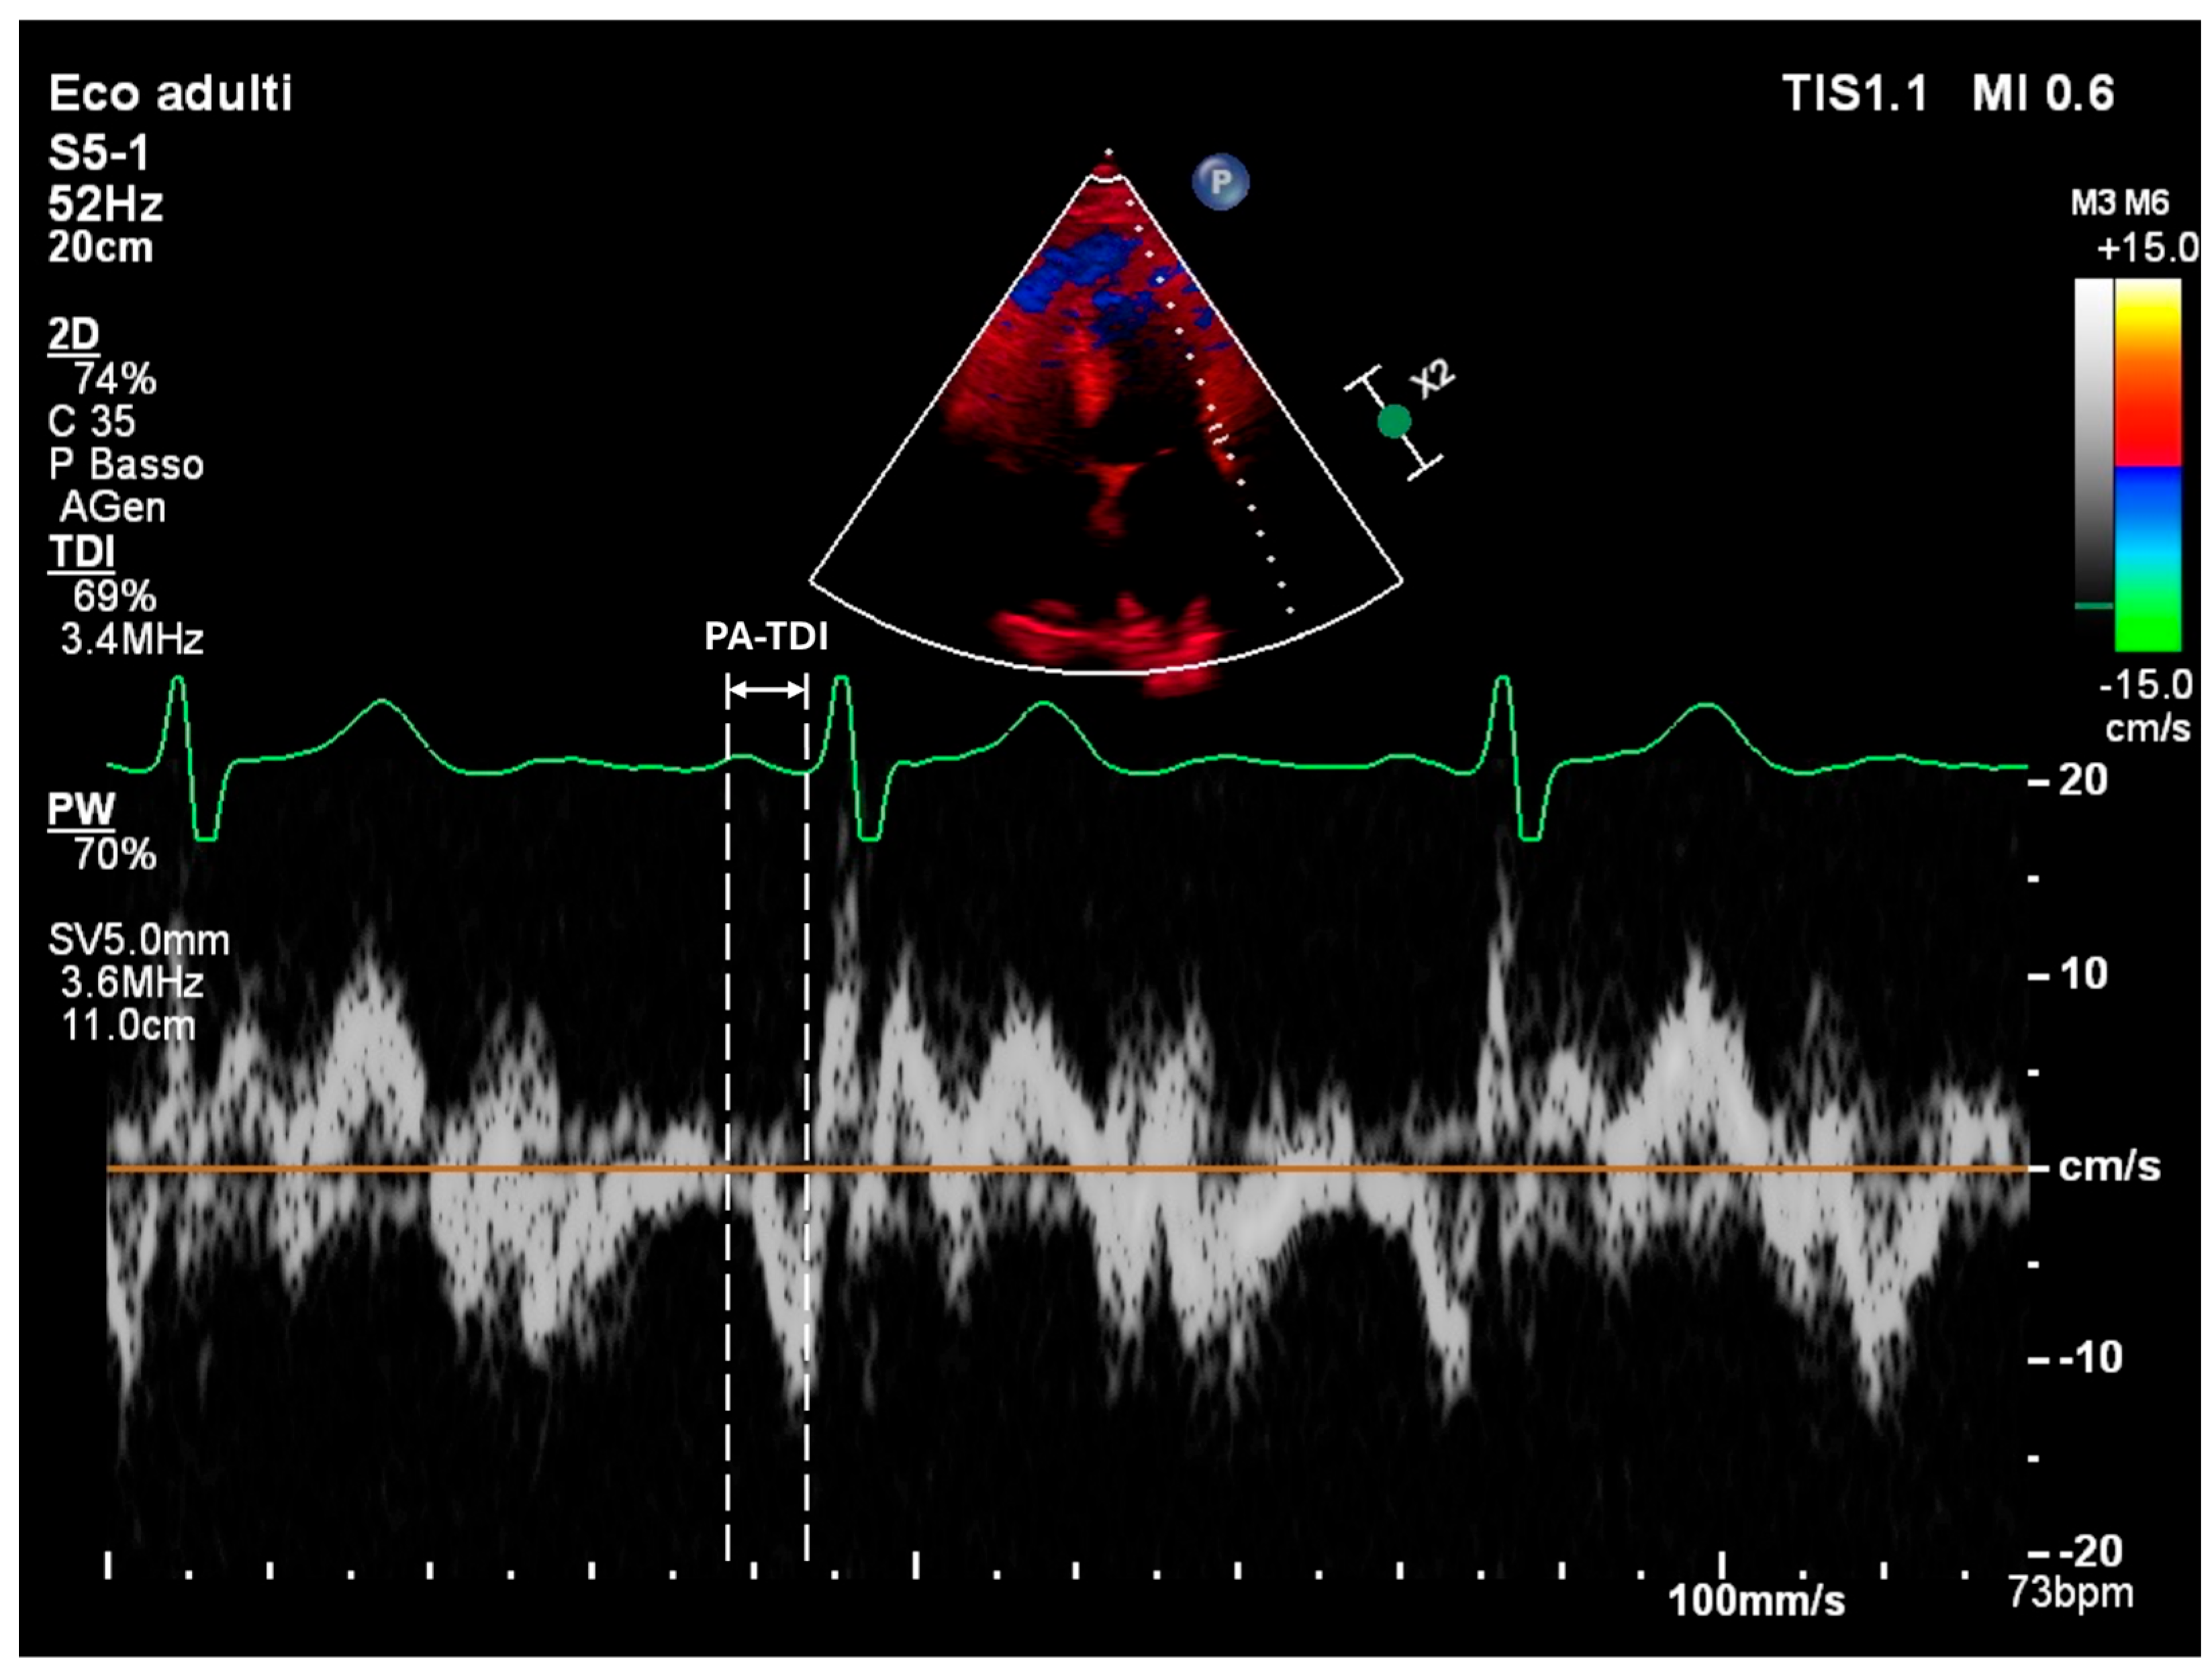

| PA-TDI | Atrial Conduction Time Measured by Tissue Doppler Imaging |

| PA-TDI (Atrial Conduction Time) | Indicates intra-atrial conduction delay and electromechanical dysfunction | Associated with prolonged activation time, interatrial dyssynchrony, and zig-zag conduction |